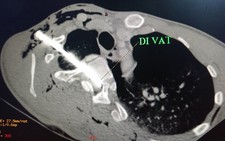

"Bệnh nhân nhập viện cấp cứu vào ngày 20-8. Khi đó bệnh nhân đang trong tình trạng nguy kịch: mắt phù nề, chảy nhiều máu. Quan sát thấy có một dị vật sắt đâm vào hốc mắt bên dưới, đẩy nhãn cầu lệch lên trên; ảnh chụp CT-scanner cho thấy dị vật đâm xuyên hốc mắt trái qua hốc mắt phải, đẩy cong dây thần kinh thị giác bên phải lên cao", bác sĩ Cảm cho biết.